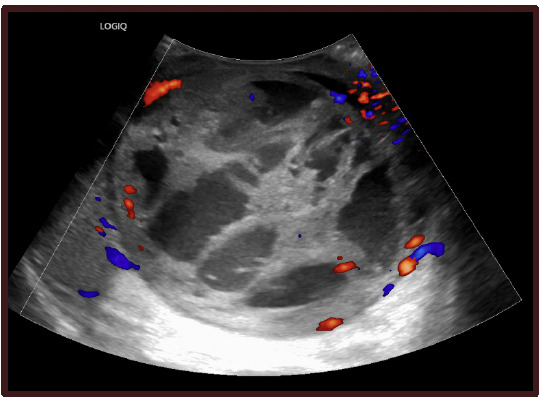

Physical examination revealed diffuse enlargement of the left hemiscrotum compared to the right, without overlying skin discoloration. Palpation of the left testicle demonstrated firmness without abnormal warmth, erythema, or tenderness. Given these findings, point-of-care scrotal ultrasound was performed, which demonstrated marked enlargement of the left testicle measuring approximately 9.0 x 10.0 cm compared to the contralateral right testicle measuring approximately 8.0 x 9.0 cm, without evidence of hydrocele or torsion. The left testicle demonstrated heterogeneous echogenicity with complex cystic areas and internal vascular septations (Figure 1). Duplex imaging further demonstrated preserved arterial and venous waveforms (Figure 2), helping exclude torsion and supporting intratesticular pathology.

The patient was advised to seek emergent evaluation, and subsequent imaging at the emergency department confirmed a 9.9 cm complex cystic mass with thick vascular septations replacing the left testicle, highly concerning for primary testicular malignancy. Serum tumor markers were elevated, including beta-human chorionic gonadotropin (β-hCG) at 39 IU/L (reference range: 0-3 IU/L) and alpha-fetoprotein (AFP) at 73.8 ng/mL (reference range: <6.1 ng/mL), and lactate dehydrogenase (LDH) at 284 U/L (reference range: 135–225 U/L) (Figure 3). Cross-sectional imaging demonstrated no evidence of metastatic disease in the chest, abdomen, or pelvis. The patient subsequently underwent left radical orchiectomy with testicular prosthesis insertion via a left inguinal incision in October 2024 without complication. Pathologic evaluation confirmed a mixed germ cell tumor measuring 9.8 x 8.0 x 7.0 cm, composed of teratoma (approximately 10%), embryonal carcinoma (approximately 85%), and yolk sac carcinoma (approximately 5%). Postoperative follow-up demonstrated appropriate surgical recovery. Staging workup revealed no evidence of metastatic disease, and the patient was referred to medical oncology for further evaluation and discussion of adjuvant management.

Ultrasound remains the first line imaging modality for evaluation of scrotal pathology due to its accessibility, high sensitivity for detecting testicular tumors, and lack of ionizing radiation.1,2 In contrast, computed tomography urograms do not routinely include detailed evaluation of the scrotum or testicles and are not appropriate screening tools for testicular malignancy.2 The absence of abnormalities on the initial CT imaging likely contributed to the delay in diagnosis. Recognition of concerning sonographic features such as heterogeneous echogenicity, cystic components, and vascular septations is critical, as these findings necessitate urgent urologic referral.2

A normal testicle on ultrasound demonstrates homogeneous medium-level echogenicity with a smooth contour and symmetric size compared to the contralateral testis. In contrast, malignant intratesticular lesions typically appear as hypoechoic or heterogeneous masses with irregular borders, internal cystic changes, and increased internal vascularity on Doppler imaging. Importantly, solid intratesticular masses are considered malignant until proven otherwise.2 Early recognition of these sonographic characteristics in the primary care setting can significantly reduce delays in diagnosis and expedite definitive management.